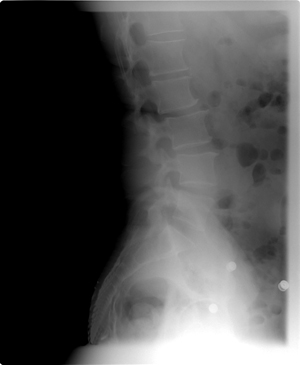

Xrays revealed my spine is bent a bit to the left, which reconciles with my muscle spasms. When they occur my right leg becomes about 1 – 2 inches shorter. I asked if chicken or egg – whether spine driven or muscle driven, the doctor thinks spine driven and correctable. Best guess is 6 to 9 treatments including pressure point massage. So, I’m going down this path. New for me. Science or art?